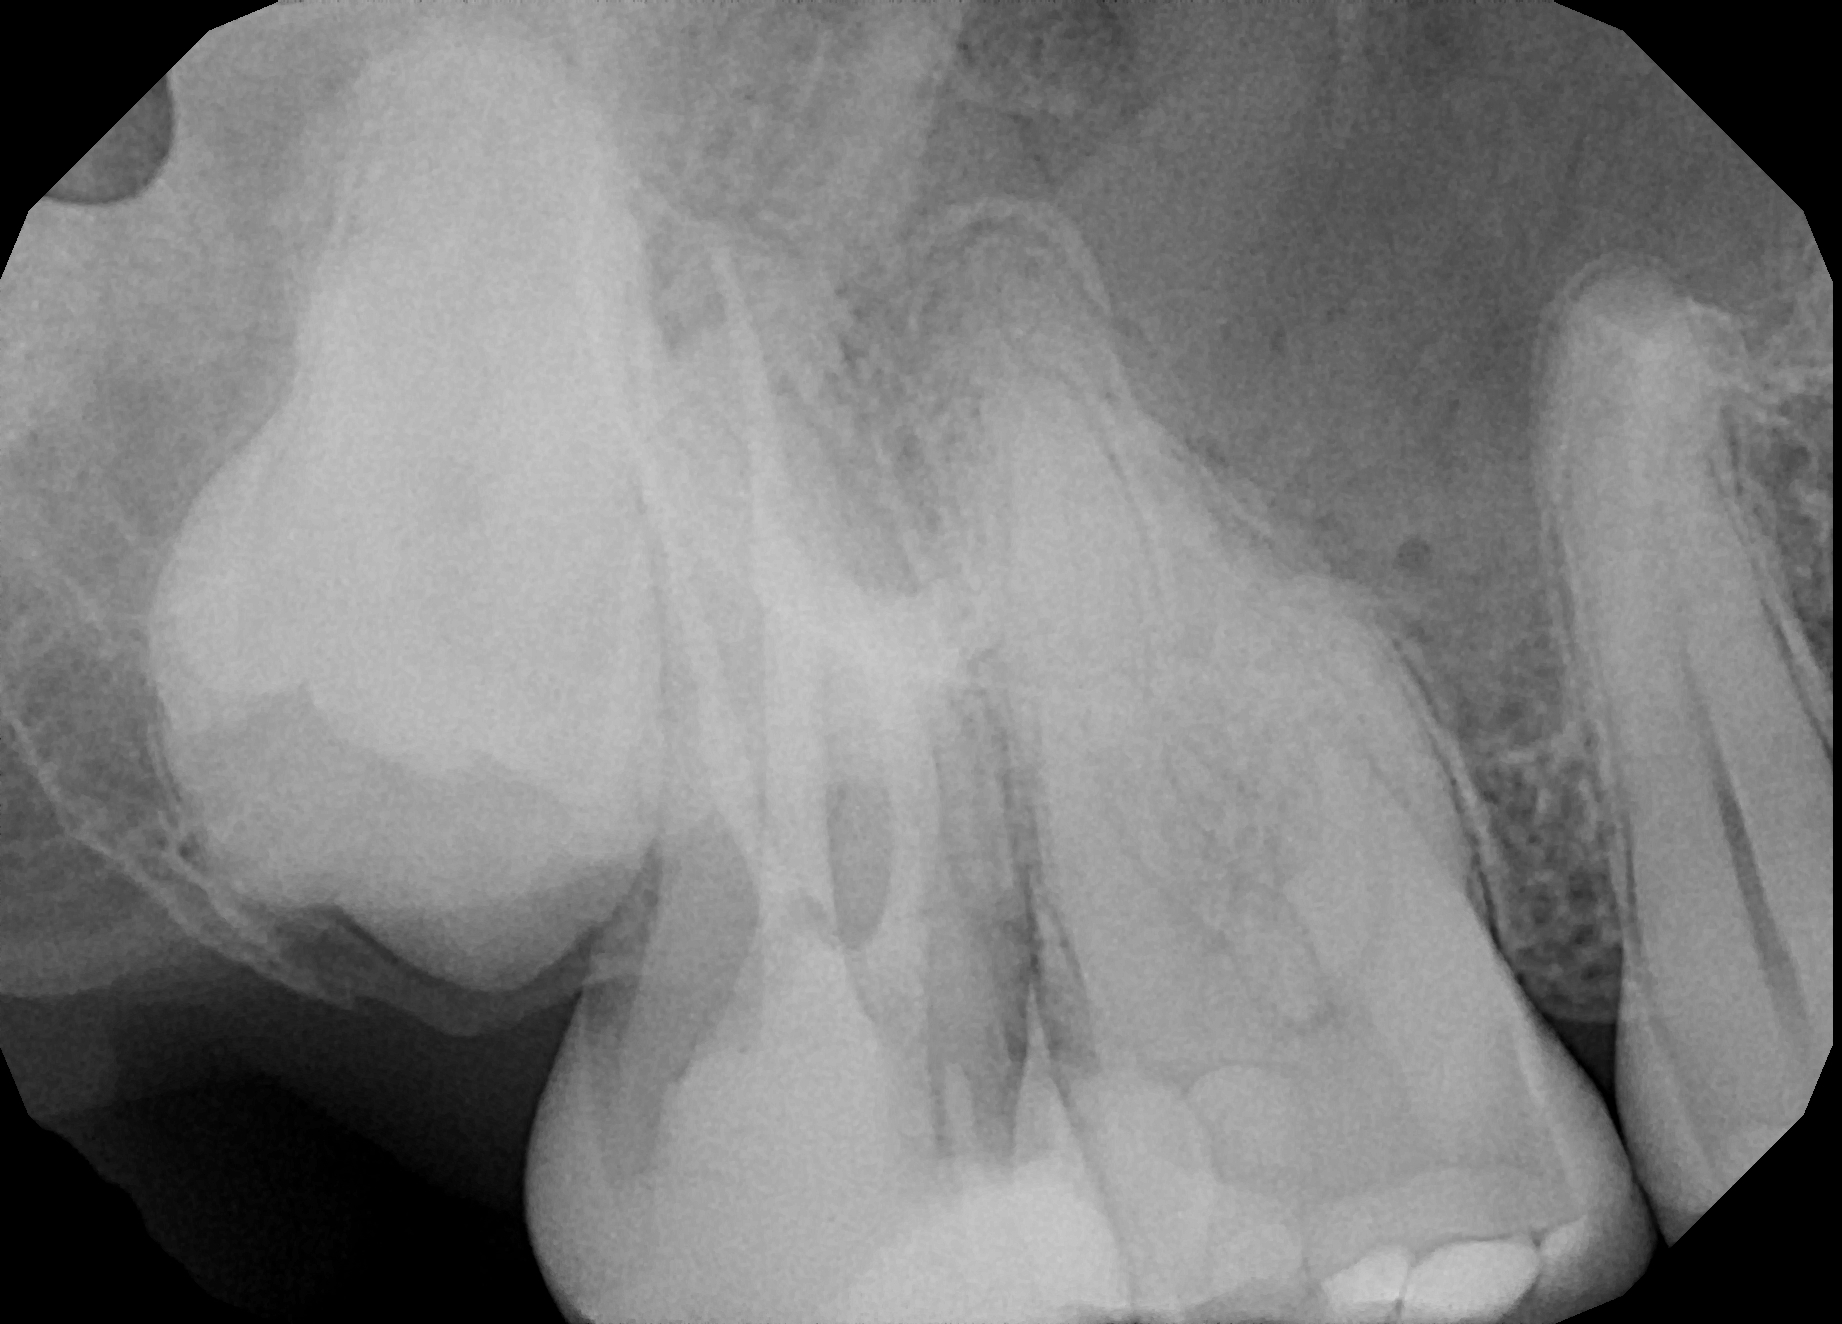

Fig.: 6

Case 1

A 43-year-old patient came to our office having been referred for endodontic treatment. During oral examination, a deep carious lesion in tooth #27 was visible. Radiographic examination confirmed the diagnosis (Fig. 6). After gingivectomy with a gingiva trimmer bur (JOTA), which was necessary in order to create space for proper isolation (Figs. 7–9), the cavity was cleaned and prepared for build-up.